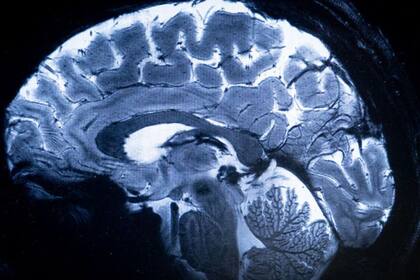

En un estudio reciente, investigadores encontraron cambios principalmente en el volumen

Sin embargo, en un estudio reciente que analizaremos con detalle más adelante, los investigadores encontraron cambios principalmente en el volumen del cerebro. Por lo que en esta ocasión, y sin que sirva de precedente, se usarán ambos términos indistintamente.

Para averiguarlo, los científicos realizaron resonancias magnéticas a 3.226 personas, mujeres (53 %) y hombres (47 %) de entre 45 y 74 años. Comparando las imágenes de los voluntarios nacidos entre las décadas de 1930 y 1970, encontraron que, en promedio, los cerebros de los participantes de los 70 presentaban un volumen un 6,6 % más grande que los de los sujetos venidos al mundo cuarenta años antes, sin diferencias significativas entre hombres y mujeres.

El crecimiento afectaría a áreas importantes como la sustancia blanca –red de axones mielinizados que permiten la comunicación entre las distintas áreas dentro y fuera del sistema nervioso–, la sustancia gris cortical –donde se llevan a cabo la mayoría de los procesos cognitivos y emocionales– y el hipocampo, estructura responsable de diversas funciones cognitivas como la memoria o la capacidad para orientarse y desplazarse.